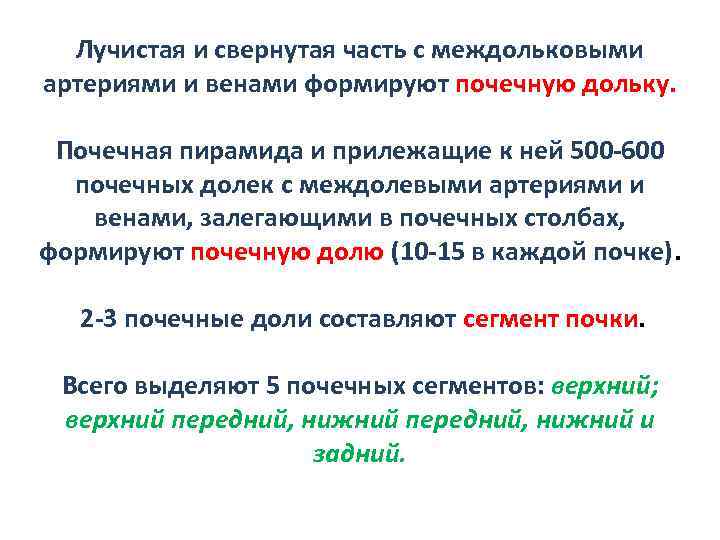

Лучистая и свернутая часть с междольковыми артериями и венами формируют почечную дольку. Почечная пирамида и прилежащие к ней 500 -600 почечных долек с междолевыми артериями и венами, залегающими в почечных столбах, формируют почечную долю (10 -15 в каждой почке). 2 -3 почечные доли составляют сегмент почки. Всего выделяют 5 почечных сегментов: верхний; верхний передний, нижний и задний.

Лучистая и свернутая часть с междольковыми артериями и венами формируют почечную дольку. Почечная пирамида и прилежащие к ней 500 -600 почечных долек с междолевыми артериями и венами, залегающими в почечных столбах, формируют почечную долю (10 -15 в каждой почке). 2 -3 почечные доли составляют сегмент почки. Всего выделяют 5 почечных сегментов: верхний; верхний передний, нижний и задний.